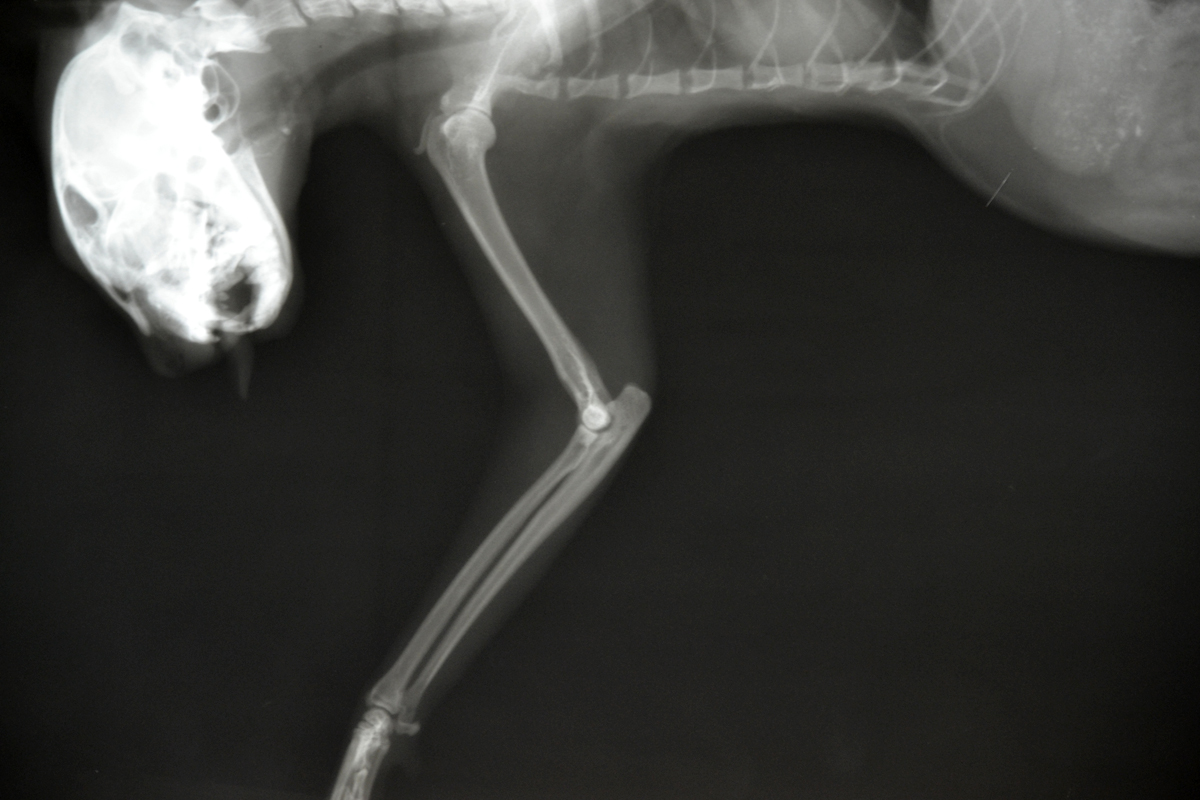

Детальное строение скелета передних конечностей кошки

Раздел: Другие животные